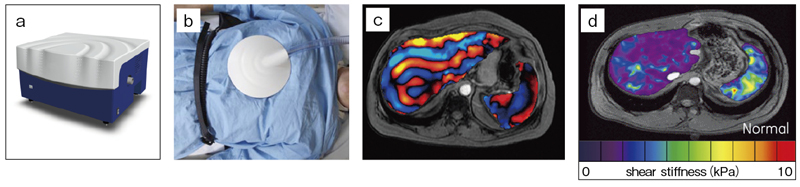

次に,MR Touchの概略を述べる。MR Touchは,MRエラストグラフィ(MRE)と呼ばれている技術を製品化したものである。肝内の線維化が進行するにつれて増していくとされる,肝臓の硬さ(弾性率)を評価する手法である。機械室に置かれた“Active Driver”と呼ばれる振動発生装置で生まれた振動波は,空気チューブを伝わってMRIガントリーへ運ばれる。空気チューブの終端には,直径15cm程度の“Passive Driver”と呼ばれるトランスデューサーがついており,これを被写体の腹部に装着することで振動を与え,その波の生体内の伝播をMRIで画像化する方法である。波の性質として,軟らかい媒体を通過するときと,硬い媒体を通過する時では,伝播する波長が異なる。この波長の違いをMRIでキャッチし,最終的に物理量としての硬さに変換する。MR Touchにおいて使用するデバイスを図8に示す。最初に得られるのが,wave imageと呼ばれる位相画像である。ここからあるアルゴリズムを使用して,せん断応力(shear stiffness)を求め,硬さの指標として表している。このMR Touchは,前述のIDEAL-IQと組み合わせて,肝臓のびまん性疾患の評価のための新たなアプローチとして期待されている。

図8 MRエラストグラフィ(MRE)において使用するデバイスと出力データ

a:振動を発生させるActive Driver b:振動を患者へ伝えるPassive Driver

c:wave image d:せん断応力マッピング